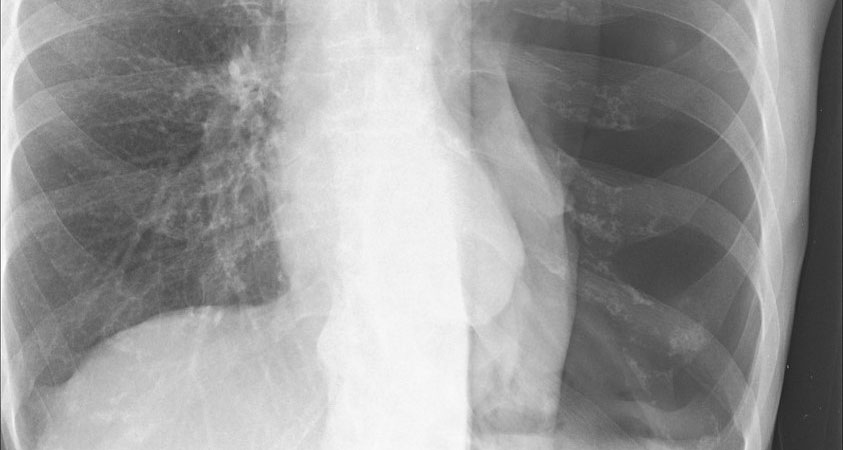

New artificial intelligence-powered technology may soon help reduce delays in diagnosing a collapsed lung, or pneumothorax, which is a serious condition that can be treated with quick intervention.

Pneumothorax occurs when air leaks into the chest cavity, compressing the lungs and causing a partial or complete collapse. Tens of thousands of Americans suffer pneumothorax each year, often from a traumatic injury, although other conditions can also result in collapsed lung.

Callcut, who is also the director of data science at the Center for Digital Health Innovation (CDHI) at UCSF, led the product development of the new AI screening tool, known as Critical Care Suite, which is being licensed by UCSF Innovation Venture to GE Healthcare. When a sick patient arrives in the emergency room, a portable X-ray embedded with the new AI can be brought to the bedside. The chest X-ray is sent immediately to a radiologist and if the AI has detected a pneumothorax, the image is moved to the top of the queue for review. The portable X-ray can also display an alert, which can help doctors at the bedside treating the patient to make more time-sensitive decisions.